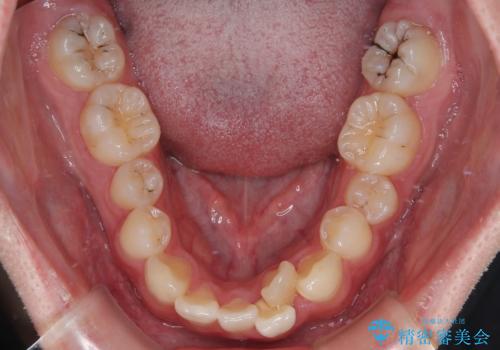

初診時の状態

・上下ともに歯がきれいに並びきらず、がたつきが見られました。

・上下の前歯の中心(正中)がずれています。

・特に上顎の幅が狭いため、下顎の歯列も内側に入り込み、歯が並ぶスペースが不足していました。